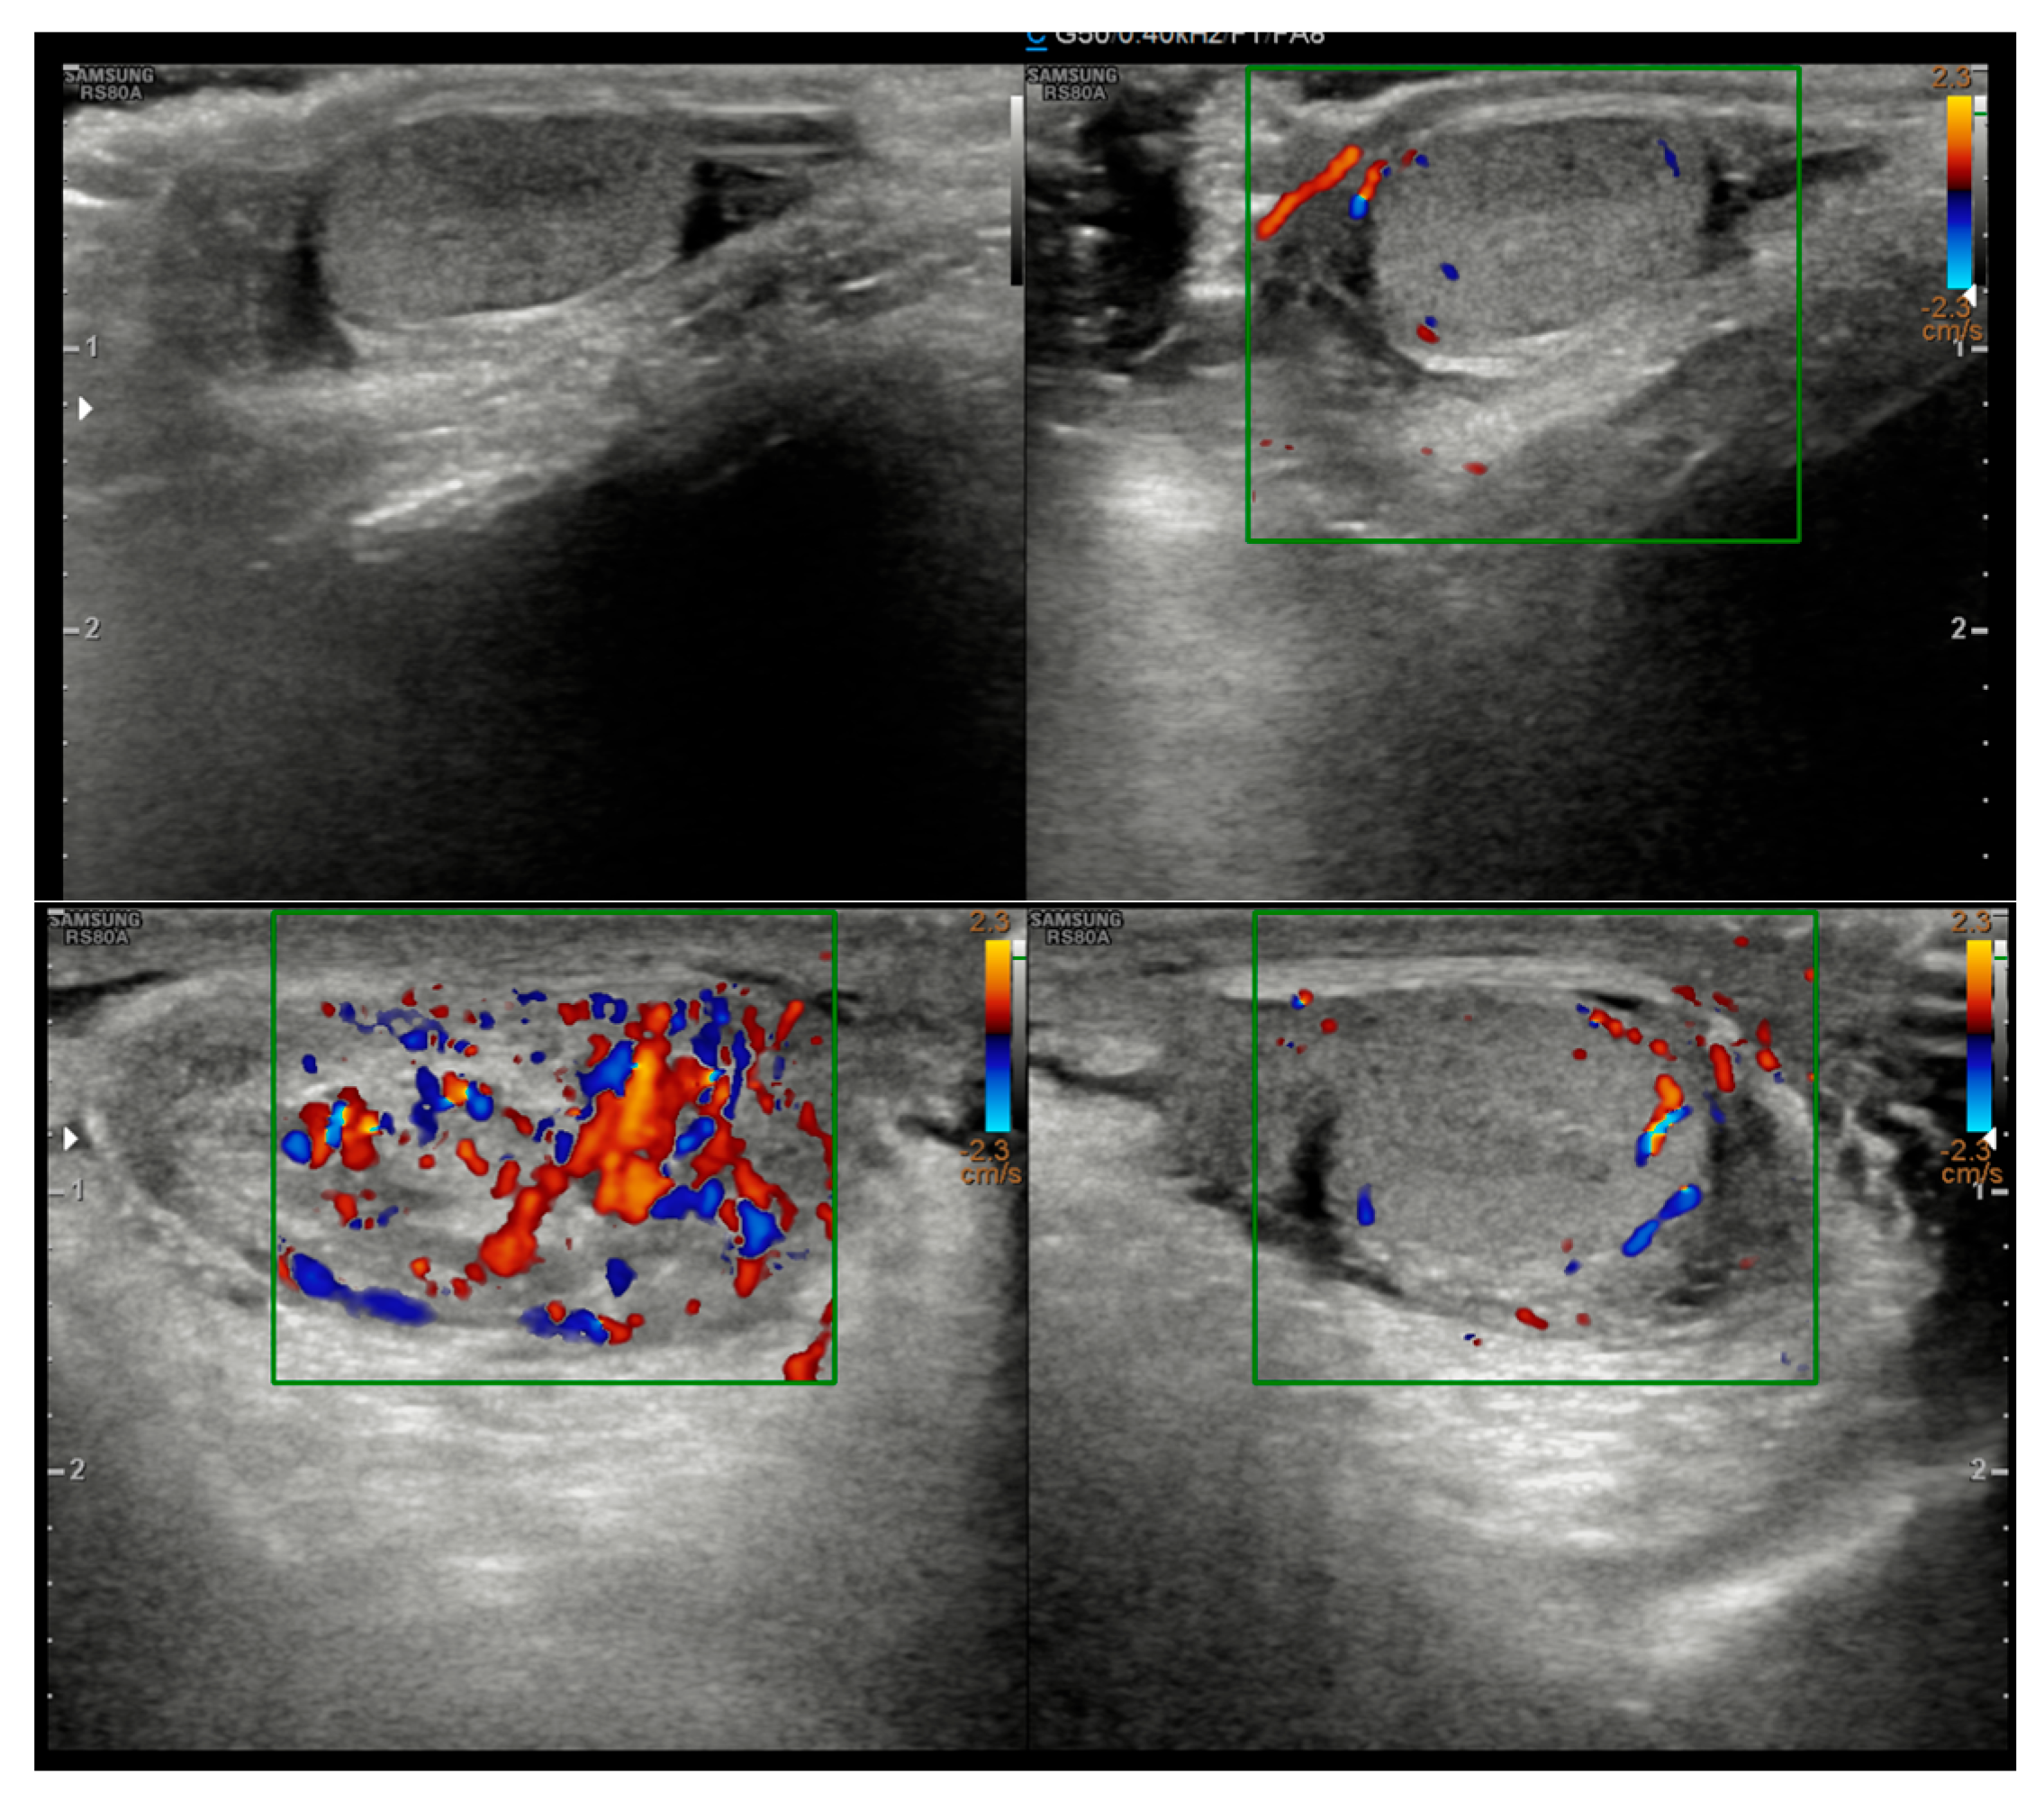

A 5-year-old boy, born in Catania, Sicily, Italy, to a Sri Lankan migrant family, was evaluated for left testicular pain and swelling. He had no prior hospitalizations or significant medical history. He was fully vaccinated. The symptoms were initially attributed to orchiepididymitis, as the left testis was edematous, painful, and hyperemic. The patient was treated with oral amoxicillin/clavulanate and nonsteroidal anti-inflammatory drugs (NSAIDs) for 10 days. There was mild improvement in swelling, but testicular pain persisted. Laboratory tests, including blood counts and inflammatory markers, showed only mild thrombocytosis (415,000/mmc). An ultrasound performed at the Pediatric Emergency Department of Garibaldi Nesima Hospital in Catania showed thickening of the left spermatic cord with increased blood flow on Doppler, while the testes appeared normal in morphology, and no hydrocele was present (Figure 1). Two weeks later, at a follow-up visit, the boy’s symptoms had worsened. A firm, elastic, mobile mass was palpated in the left inguinal/scrotal area, distinct from the right testis. The testis ultrasound at that time revealed a well-defined, round hypoechoic mass (measuring 8.5 mm) with linear hyperechoic structures within it (Figure 2).

Figure 1.

Initial ultrasound showing a thickened left spermatic cord with increased vascular signals.